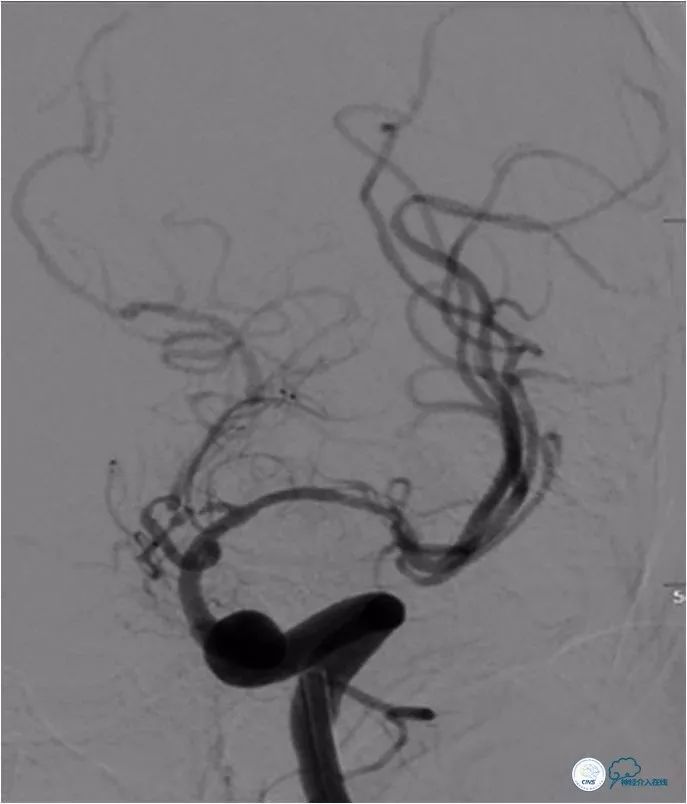

予替罗非班(动脉内6ml,静脉推注6ml并持续静脉泵入6ml/h)。观察10分钟后,再次造影提示狭窄段未见明显弹性扩缩(图11,12)。

图11

图12